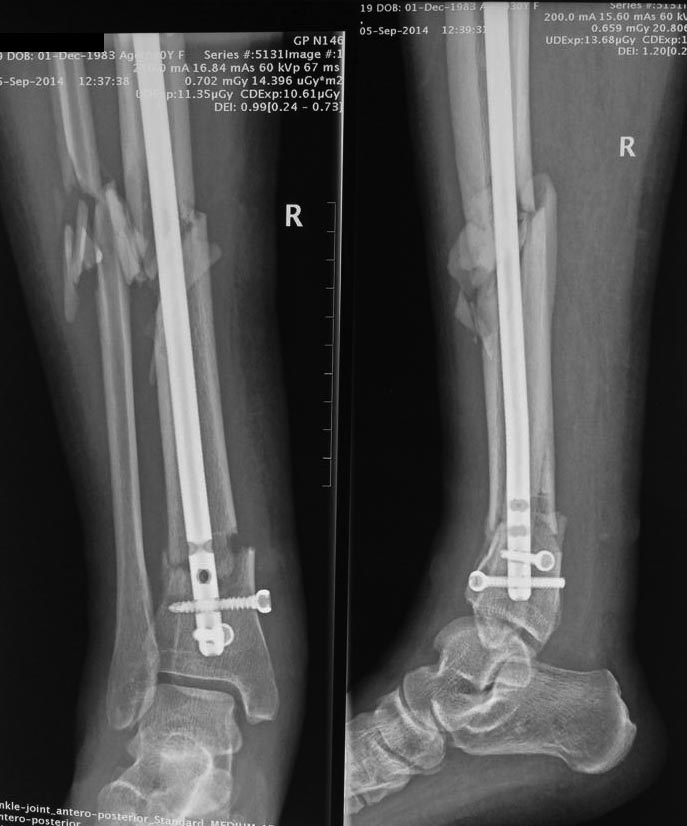

[Ortho] Остеосинтез tibia стержнем 2,5 мес., свищи

Что посоветуете, друзья. Оперировалась 2,5 мес назад, в одной из

московских клиник, при ранней активизации через 1,5 мес появилась такая

деформация, плюс имеются в области нижней трети голени свищи с

незначительным отделяемым